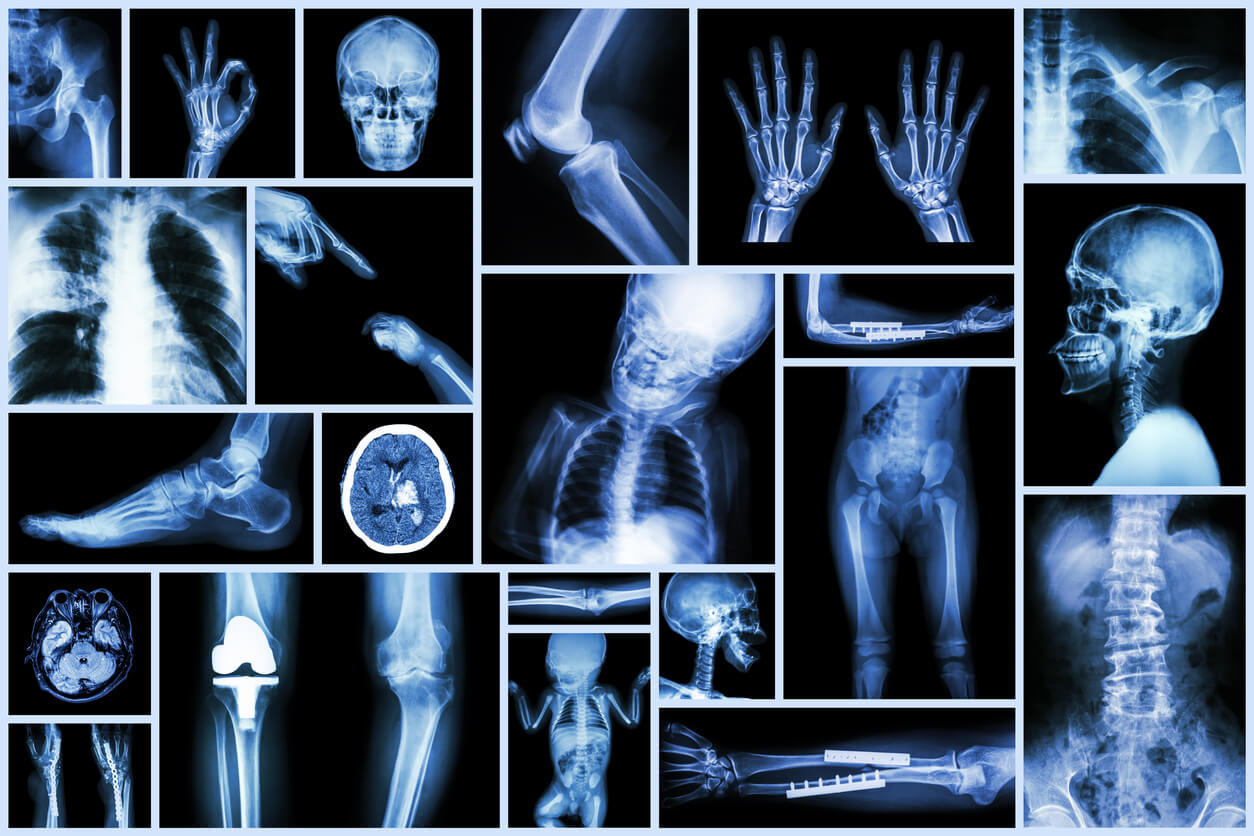

Al igual que cualquier otro estudio de imágenes, las radiografías nos permiten conocer aspectos del organismo de los niños que no podemos ver a simple vista.

En la sala de emergencias, una radiografía nos ayuda a confirmar el diagnóstico de una fractura, la presencia de un cuerpo extraño en la vía aérea o definir que un dolor abdominal requiere un tratamiento quirúrgico.

En otras áreas y disciplinas médicas, los rayos X han aportado un sinfín de beneficios y de eso podemos estar seguros. Además, son estudios rápidos, económicos, disponibles en la gran mayoría de los centros asistenciales y que, en general, no requieren procedimientos de sedación o anestesia.